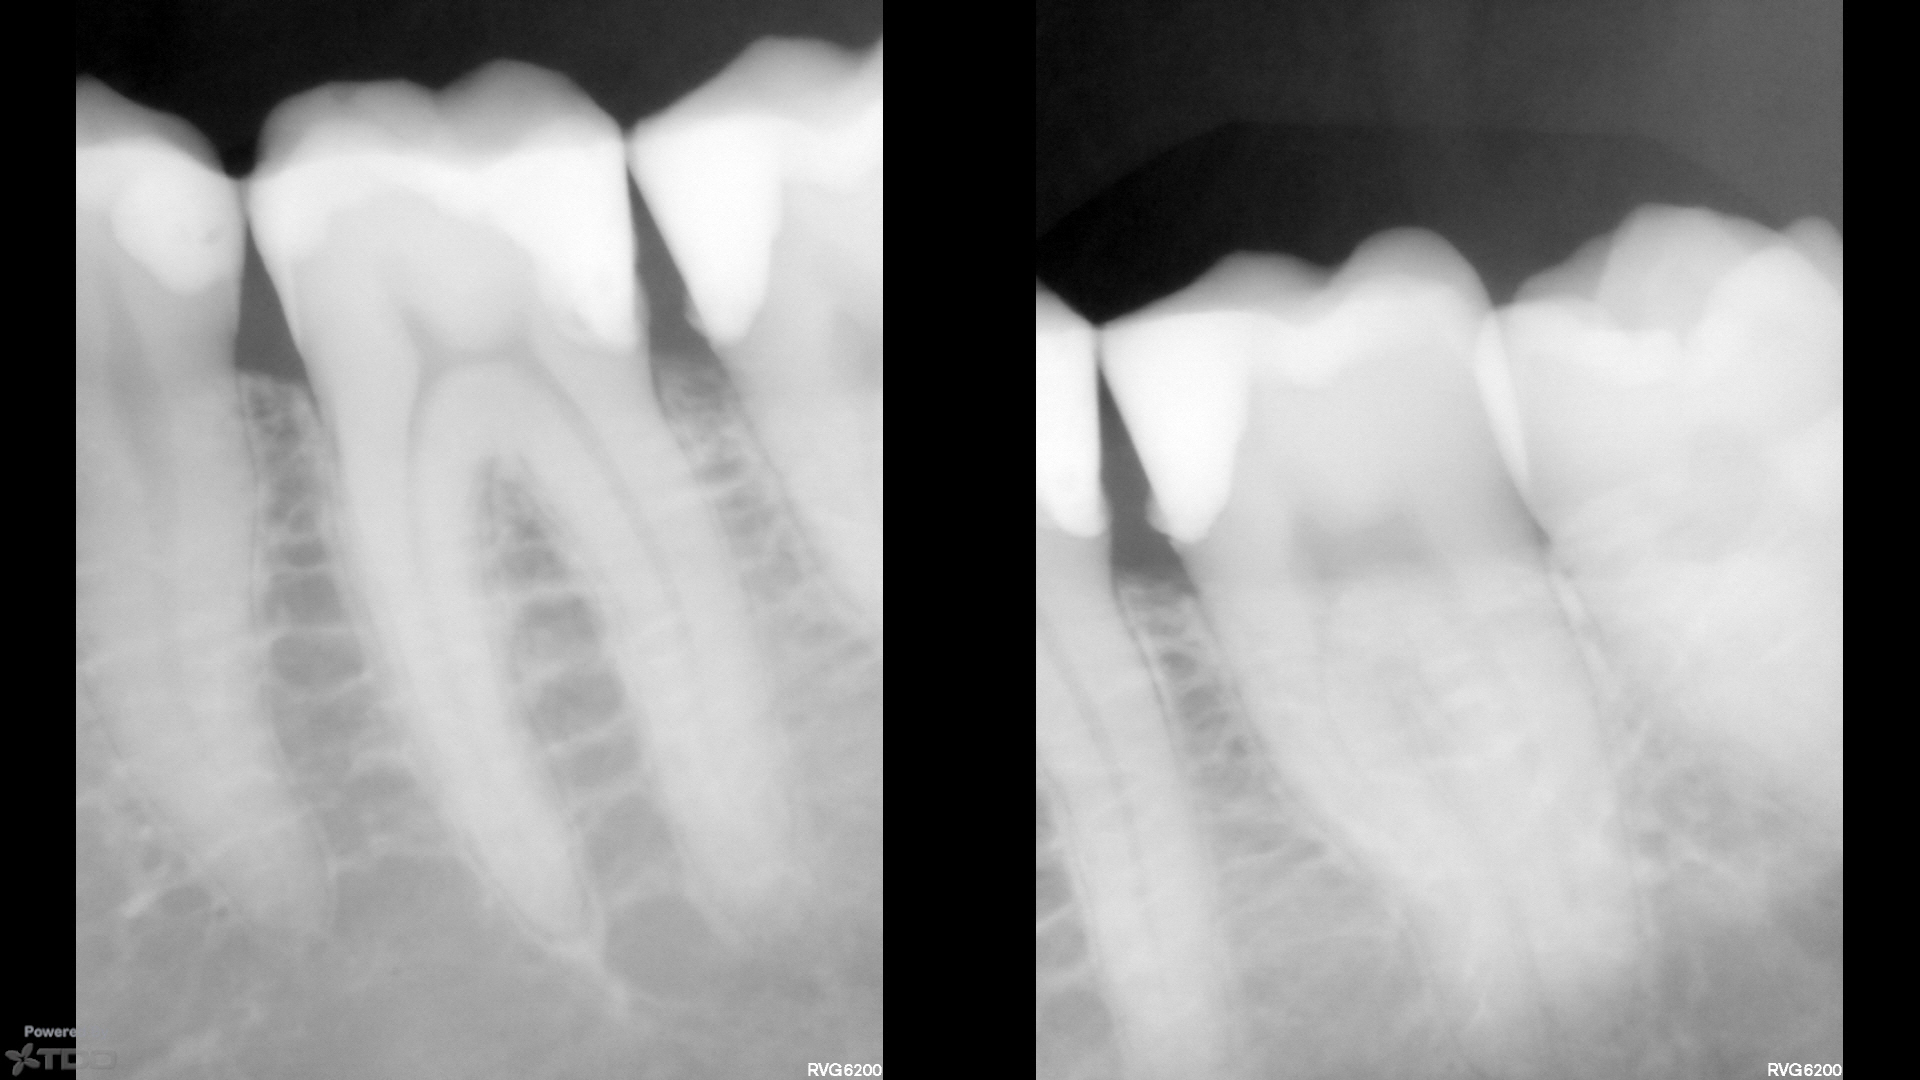

My mind reading powers are non existent but my visual ones suggest all good apart from the apparent difficulty of contouring to keep the contact shape with the matrix used in this case to prevent food packing.

Looks like you don’t need mind-reading powers as you got it. Also…looks like some surplus material too… This is a setup for a recurrence of the problem that created the problem that created this problem…